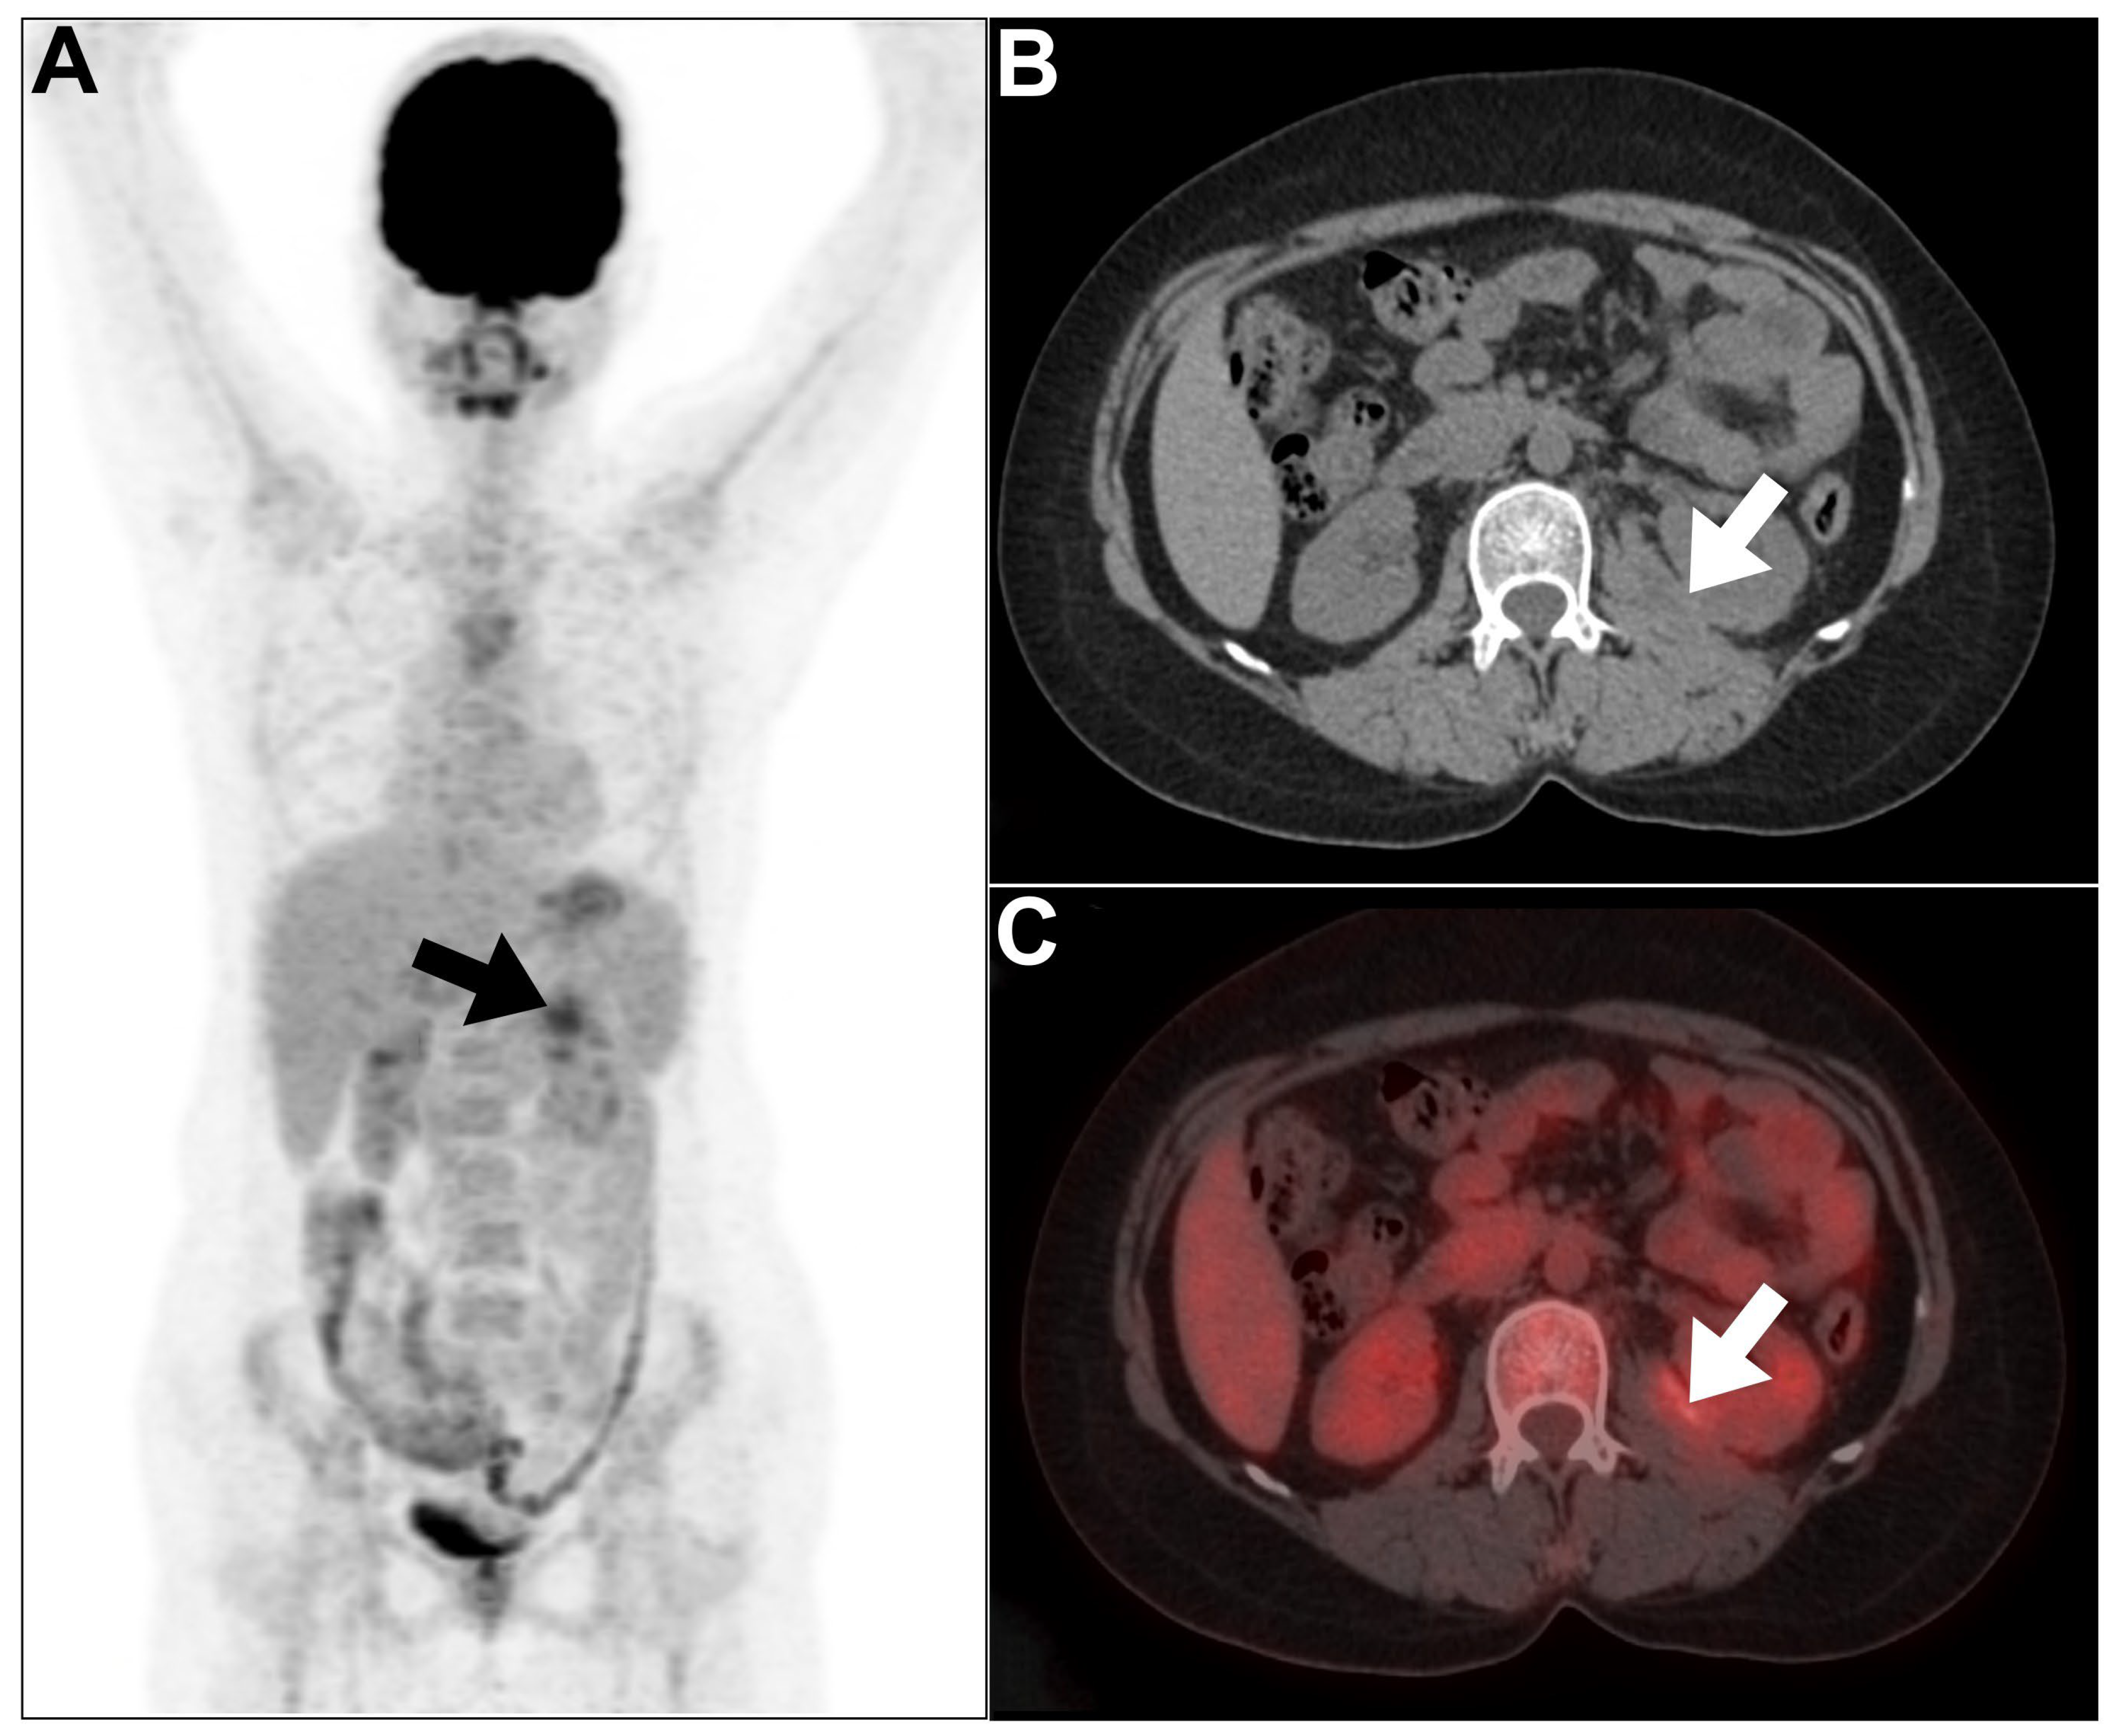

- Joshi, P.; Lele, V.; Shah, H. Fluorodeoxyglucose positron emission tomography-computed tomography findings in a case of xanthogranulomatous pyelonephritis. Indian J. Nucl. Med. 2013, 28, 49–50. [Google Scholar] [CrossRef] [PubMed]

- Liu, Y.; Tong, G.; Wen, Z. Focal Xanthogranulomatous Pyelonephritis on FDG PET/CT. Clin. Nucl. Med. 2022, 47, e611–e612. [Google Scholar] [CrossRef]

- Swingle, C.A.; DBaumgarten, A.; Schuster, D.M. Xanthogranulomatous pyelonephritis characterized on PET/CT. Clin. Nucl. Med. 2005, 30, 728–729. [Google Scholar] [CrossRef]